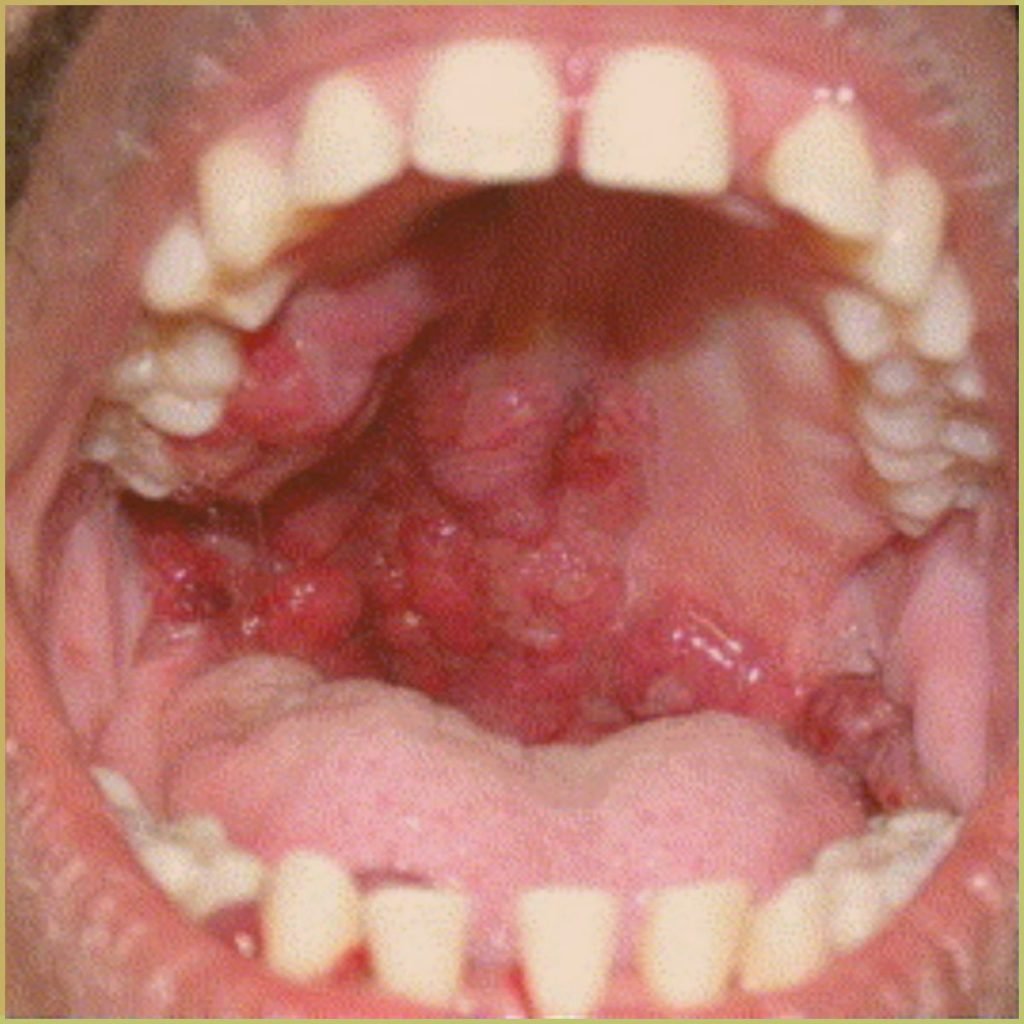

PYOGENIC GRANULOMA

Pyogenic Granuloma (granuloma pyogenicum) refers to a benign vascular tumor that is not pyogenic or granulomatous. It is caused by a hyperplastic reaction of capillaries and fibroblasts to chronic trauma/irritation. The exact mechanism is unknown, but pyogenic granulomas are linked to pregnancy, trauma, and immunosuppression, as well as certain medications such as retinoids, antiretroviral drugs, and oral contraceptives. The common clinical presentation includes:

- Lesions are most frequently located on oral gingiva.

- Can be found on the lips, tongue, buccal mucosa, palate and skin.

- Red, lobular to smooth appearance.

- May be sessile to pedunculated when found on the gingiva.

- May have an erosive surface and tendency to bleed.

- Covered by a yellow fibrinous exudate when ulcerated.

- Usually asymptomatic.

Diagnosis is based on the lesion history, clinical presentation and microscopic findings, which may include:

- Hyperplastic granulation tissue (aggregates of capillary-sized vessels).

- Scattered fibroblasts and a variegated inflammatory infiltrate.

Your differential diagnosis should include:

- Peripheral giant cell granuloma.

- Peripheral ossifying fibroma.

- Kaposi’s sarcoma.

- Vascular malformation (hemangioma).

Treatment options include:

- Surgical excision (extended to the periosteum or periodontal ligament).

- Laser ablation.

- Electrosurgery.

Lessons may occasionally return.